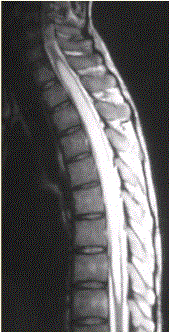

问题 患者女,45岁,胸部不适。影像学检查结果如下图所示。 病变的诊断为

选项 A.星形细胞瘤 B.室管膜瘤 C.脊髓空洞 D.髓内寄生虫 E.成血管细胞瘤 F.脊髓内转移瘤

答案 E